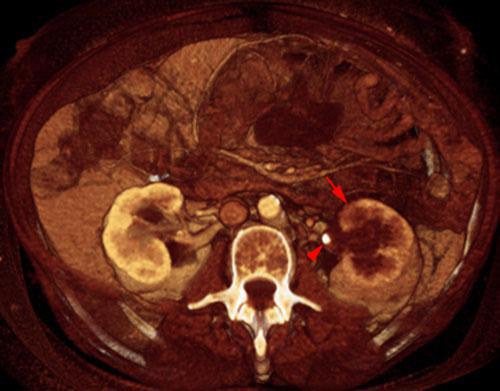

Obstrucción renal en duplicidad. Absceso renal